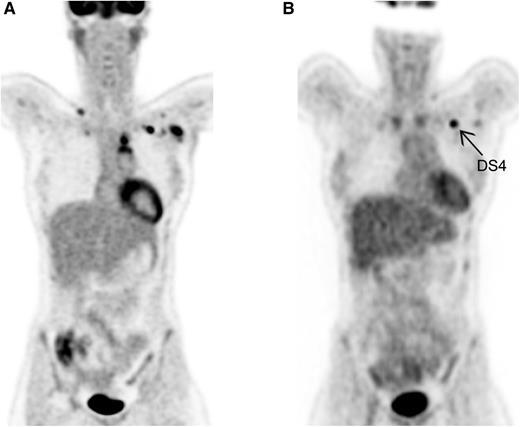

Visual assessment by DS. (A) Baseline PET in HL. Ann Arbor stage II. (B) Interim PET in HL. Partial metabolic response; left infraclavicular lymph node DS4.

HL is known as the best curable subtype of malignant lymphomas and as a disease often affecting young adults. Personalized PET-guided treatment is currently the scope of many large international trials, mainly to diminish early and late toxicity of treatment, while maintaining the relatively good outcome. Accurate staging is of utmost importance to selecting the appropriate treatment regimen, which nowadays consists of 2 to 4 cycles of ABVD and radiotherapy for early-stage HL, and, for advanced-stage HL, mainly chemotherapy (6-8 cycles of ABVD or 6 cycles of bleomycin, etoposide, doxorubicin, cyclophosphamide, vincristine, procarbazine, and prednisone [BEACOPP] escalated). With the introduction of PET using 2-deoxy-2-[18F]fluoro-d-glucose (FDG) in the mid-1990s, and PET-CT (with low-dose unenhanced CT) in the last decade, it became clear that by metabolic imaging, additional lesions could often be detected, especially in extranodal sites such as bone marrow and spleen.2 Although for patients already diagnosed with advanced-stage disease based on CT this extension will not change the Ann Arbor stage, for an accurate evaluation after treatment, the optimal comparison should be performed using the same modalities. The revised Cheson criteria, published in 2007, advised using FDG-PET (optional) for staging and as mandatory for evaluation of treatment.3 However, the recently published Lugano criteria describe PET-CT as the modality of choice for staging and evaluation during and after treatment.4 For the visual assessment of PET-CT, a 5-point scale (also called Deauville score [DS]) grading FDG uptake compared with physiological uptake in mediastinum and liver was introduced as a new scoring system.5 No FDG uptake or minor uptake less intense than the mediastinum are graded as DS1 and DS2, respectively. Lesions with FDG uptake between mediastinum and liver are assessed as DS3. Uptake more intense than physiological uptake in the liver is scored as DS4 (see figure), and DS5 is scored for very intense uptake or appearance of new Hodgkin-related lesions.